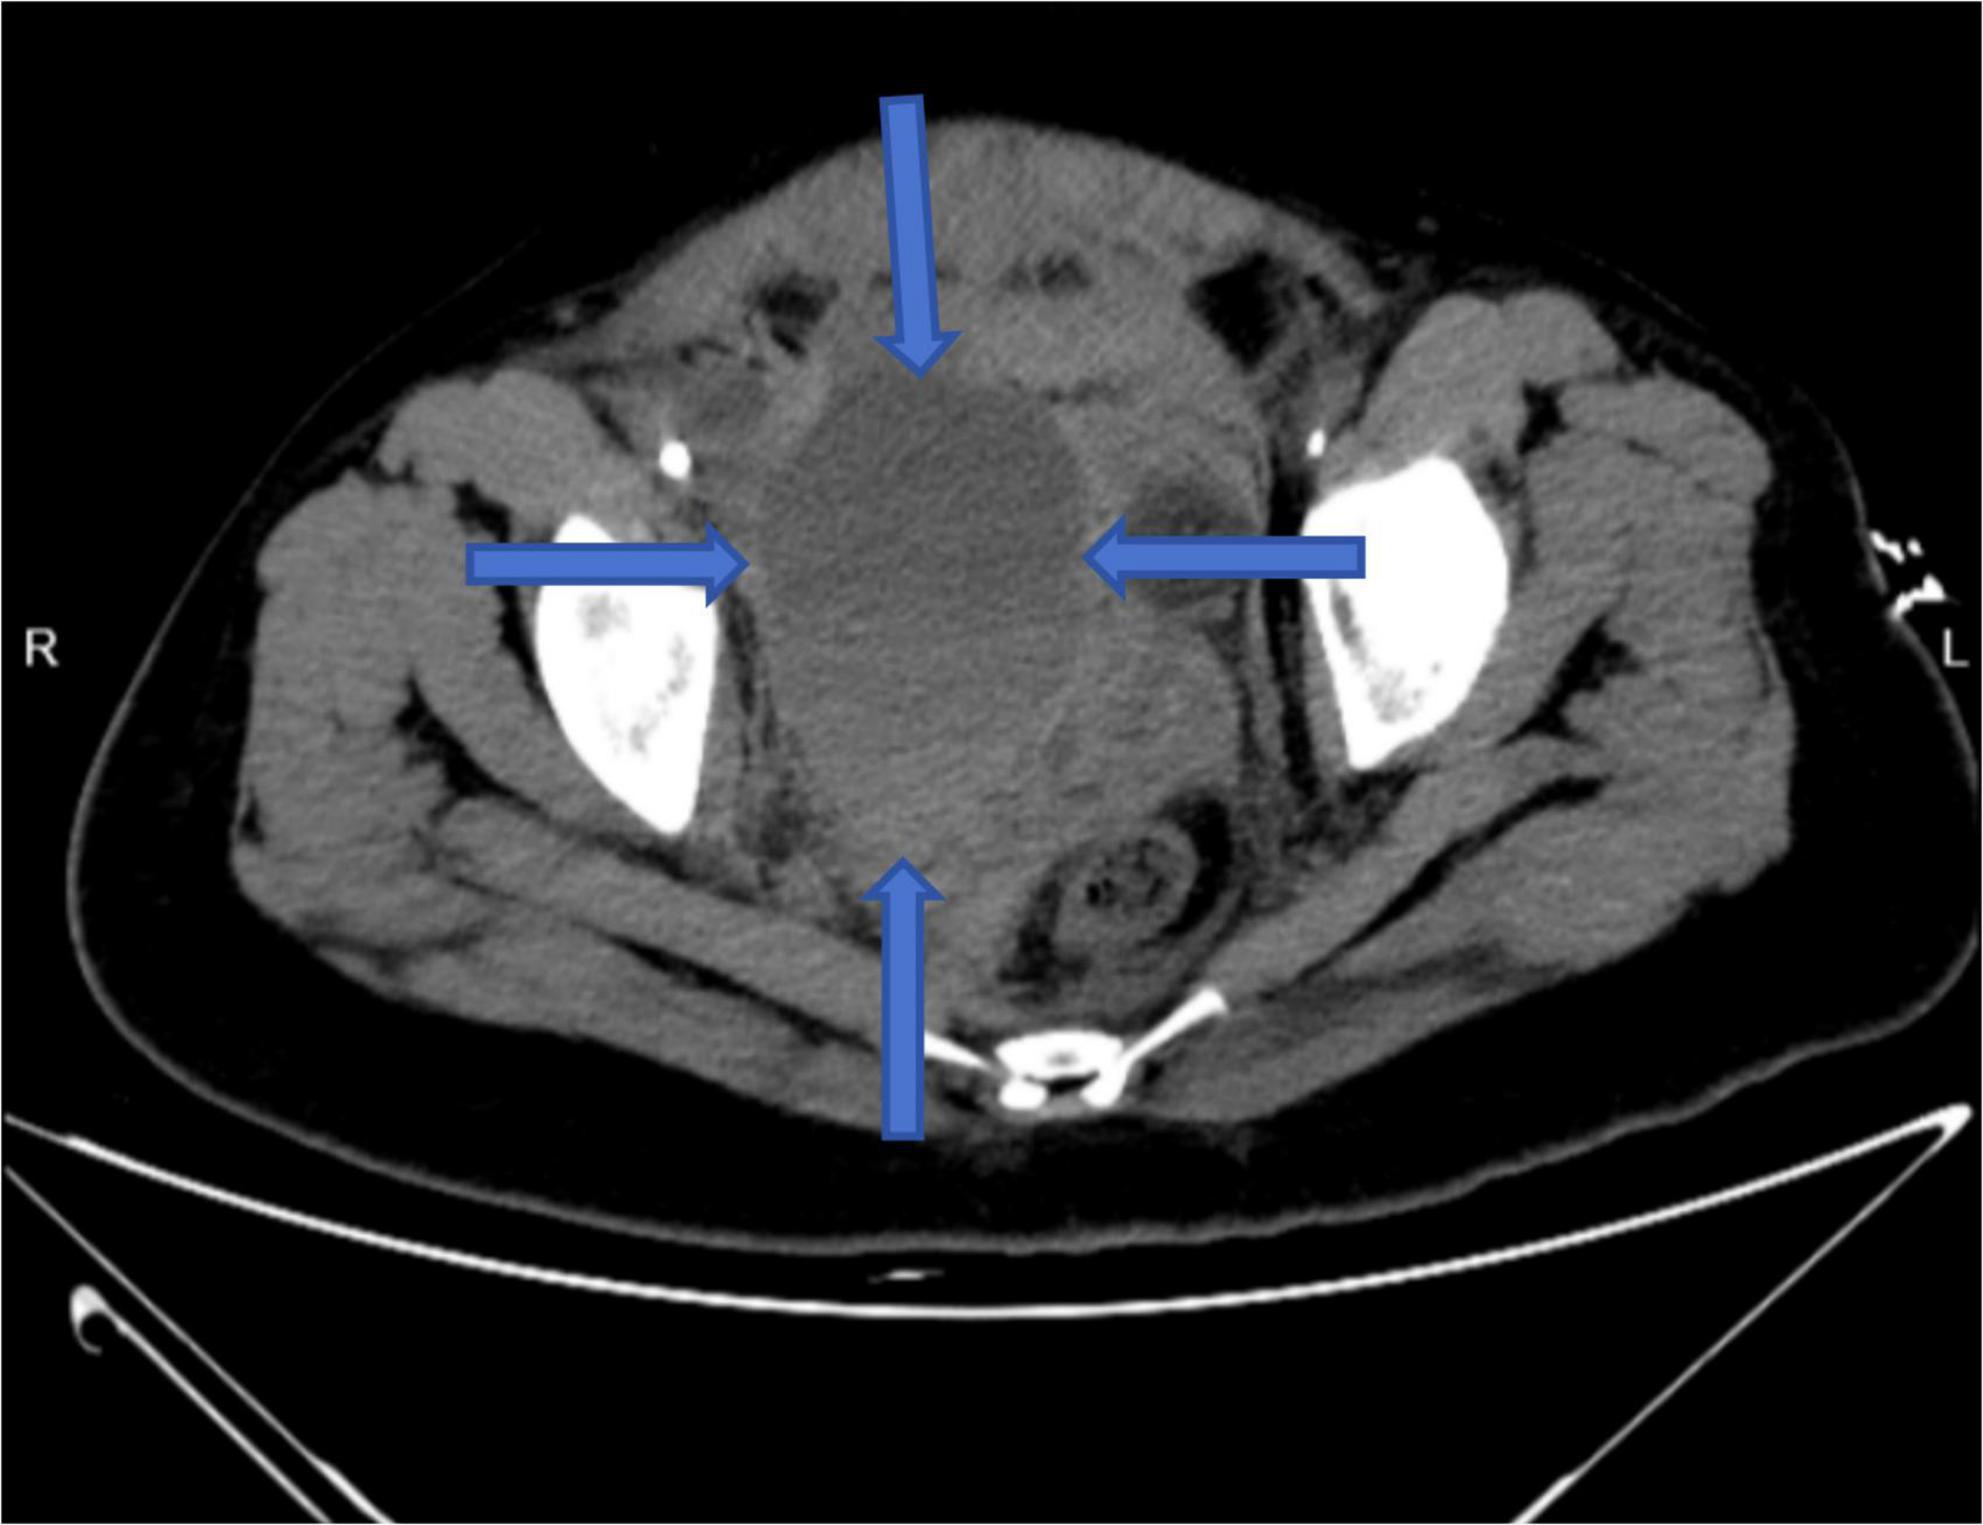

Resuscitation included fluid replacement, transfusion of leukocyte-depleted red cells and fresh frozen plasma, and norepinephrine infusion. Bedside ultrasound showed intra-abdominal fluid and a hypoechoic pelvic mass. Abdominal CT confirmed hemoperitoneum with loculated fluid collections up to 106 × 77 mm. Emergency digital subtraction angiography (DSA) was performed (Figure 3).

DSA revealed no extravasation along the venous access or iliac vein trajectory. The right femoral, common iliac, and external iliac arteries appeared intact. However, active contrast extravasation was identified in a branch of the right internal iliac artery. Endovascular embolization was performed, yielding immediate hemodynamic improvement (Figure 4). Post-procedure HGB levels stabilized between 72–77 g/L at 1, 4, and 10 h postoperatively, and the patient’s condition gradually improved.